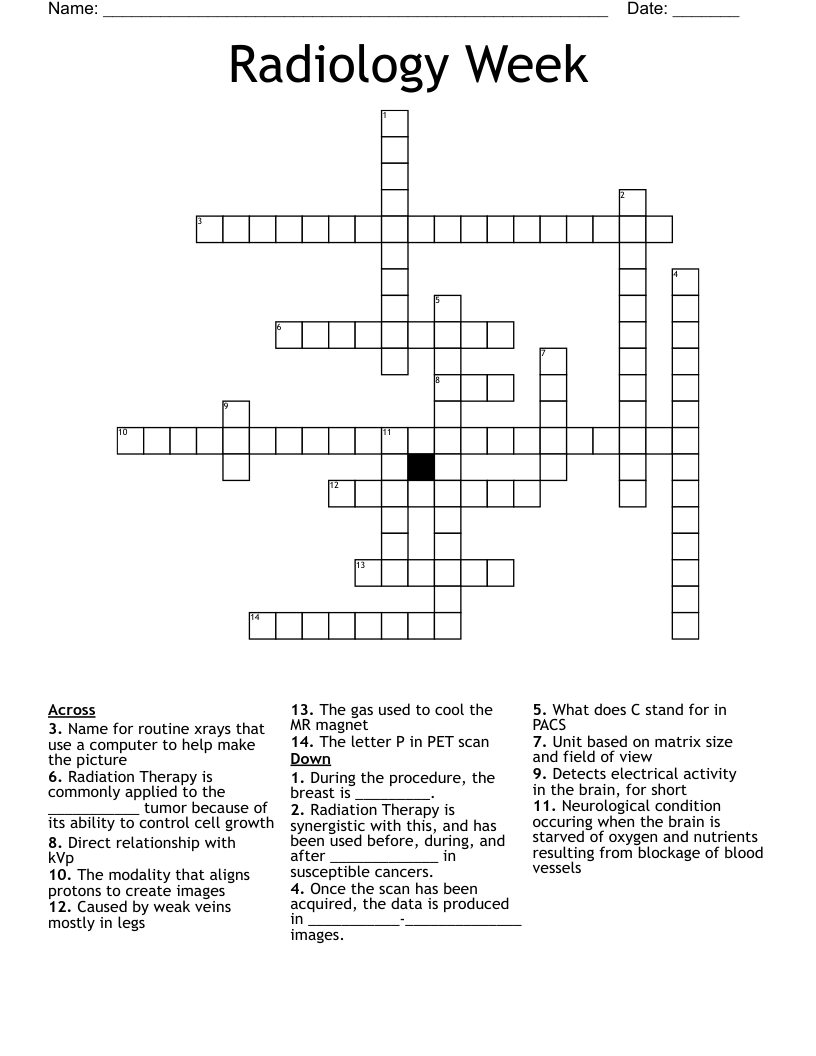

Radiology Week Crossword WordMint